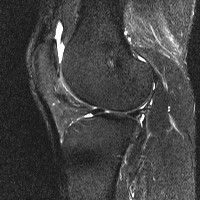

무릎 mri 간단히 봐주실 수 있으시나요 ㅠㅠ

안녕하세요 8년전 십자인대 수술하고 최근 무리한 운동에 무릎 불편감이 생겨서

mri 찍었습니다.

진단결과는 첫 찍은 병원에서 활액막염 이라는 진단을 받았습니다. 혹시 봐주실 수 있으실까요?

올라온 MRI가 단편적이라서 정확한 진단에 어려움이 있지만 십자인대에는 큰 이상이 있지는 않은것 같으며, 무릎관절내 물이 있는 것으로 보아 활액막염의 진단이 맞을 것 같습니다.

하지만 단편적인 영상이기 때문에 촬영병원에서 정확한 판독지 등을 받으시는 것이 좋겠습니다.